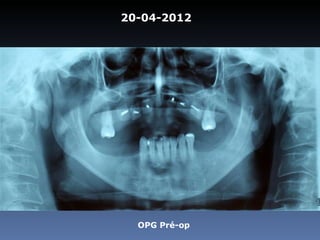

20-04-2012

OPG Pré-op

Dominga Maria silva

Idade – 53 anos

Sexo – Feminino

Raça – Caucasiana

ASA – II

Data- 23-04-2012

Diagnóstico:Desdentada parcial maxila

Plano de tratamento:      Reabilitação com 6 blocos

“onlay” provenientes de Úmero fresco-congelado

(FFB); reabertura para instalação de 6 implantes

dentários endo-ósseos e reabilitação protética fixa.